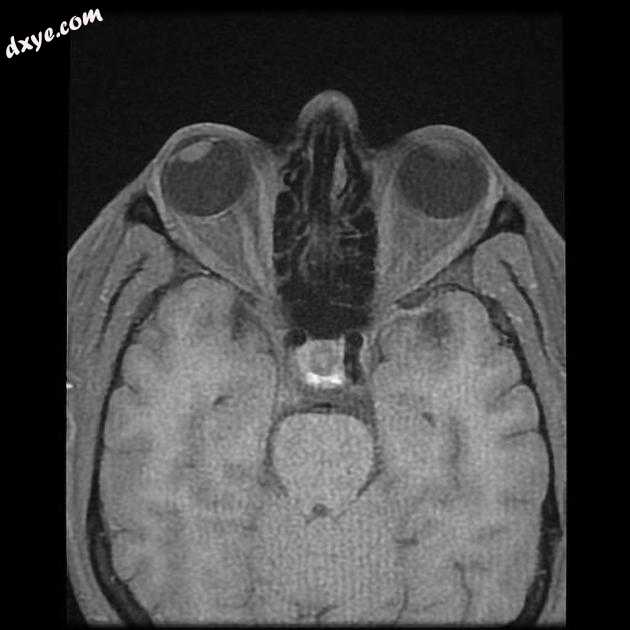

Axial FIESTA

MRI 序列显示右侧颈内动脉的部分血栓囊状动脉瘤位于 C6/7 节段的交界处,大小为 11 x 7 毫米,颈部为 2.5 毫米,压迫动眼神经 (III) 的相邻节段,在 T1 上清晰可见和 FIESTA 序列。

位于 C6/7 交界处的右侧颈内动脉部分血栓囊状动脉瘤的 MRI 特征,压迫同侧动眼神经 (III)。